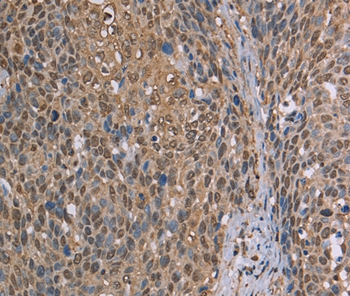

Immunohistochemical analysis of paraffin-embedded Human cervical cancer tissue using #37736 at dilution 1/50.